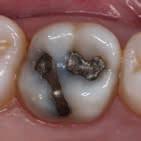

Fig. 2. Med udgangspunkt i tænder med stigende sammenbrud af en dentineksponeret carieslæsion kan et forventeligt billede af et fremadskridende mønster af ubehandlet caries fremstilles. Jo flere sammenbrudte dentinflader, desto mere åbenlæsions-topologi (A-E). I forhold til radiologisk penetrationsdybde tæt på pulpa vil dybdelæsioner med synlig radioopak zone mellem læsion og pulpa have lav risiko for bakterier i pulpa (F) overfor ekstremt dybe læsioner, der har radiologisk kontakt til pulpa (G). Læsionens topologi har konsekvenser for vækstbetingelserne af en biofilm. ”Lukkede” dentin-caries-læsioner har tydelig biofilmakkumulering, blød gullig/lysbrun dentinoverflade og med et underminerende spredningsmønster langs med emalje-dentin-grænsen (H). I modsætning til ”åbne” læsioner, der er mere mørkfarvede uden nævneværdig akkumulering af biofilm (I). (Med tilladelse fra (16) og Wiley).

Fig. 2. A picture of a progressing pattern of one untreated caries lesion is expected based on teeth with increasing break-down of a dentine-exposed carious lesion, and this is confirmed in this figure. The more surfaces that are involved in a cavity the more “open” topology (A-E). In relation to the radiological penetration depth close to the pulp, deep lesions with a visible radiopaque zone between the lesion and the pulp will have a low risk of bacteria in the pulp (F) compared to extremely deep lesions that have radiological contact with the pulp (G). The topology of the lesion has consequences for the growth conditions of a biofilm. "Closed" dentin caries lesions have clear signs of biofilm accumulation, a soft yellowish/light brown dentin surface and with an undermining spreading pattern along the enamel-dentine border (H). In contrast to “open” lesions that are darker in colour without appreciable accumulation of biofilm (I). (With permission from (16) and Wiley).

filmen, og deres produktion af organiske syrer fører til demineralisering af de hårde tandvæv (emalje, dentin og cement). I begyndelsen vil demineraliseringen ikke føre til en egentlig kavitetsdannelse på tandoverfladen til trods for, at der både er mineraltab i emalje og dentin, men den gradvise demineralisering over tid vil ubehandlet kunne svække emaljelæsionens centrale dele. De mastikatoriske kræfter vil føre til dannelse af mikrokaviteter efterfulgt af egentlige kliniske kaviteter (Fig. 1). På sigt fører dette til, at den demineraliserede emaljelæsion bryder sammen og eksponerer den underliggende demineraliserede dentin. På dette tidspunkt siges læsionen at være kaviteret eller klinisk dentin-eksponeret. Hvorvidt en carieslæsion progredierer eller ej, beskrives konceptuelt med begrebet “cariesaktivitet” eller “læsionsaktivitet”. Begrebet dækker både over, hvorvidt der ses akkumulering af biofilm på overfladen af carieslæsionen, samt hvorvidt man klinisk kan se tegn på aktiv produktion af syre i den akkumulerede biofilm. Cariesaktivitet kan tillige bekræftes radiologisk (Fig. 1A og B). En aktiv carieslæsion er kort sagt dækket af en cariogen biofilm og vil derfor progrediere med øget penetrationsdybde af læsionen til følge, hvorimod en inaktiv carieslæsion ikke på samme måde har en overfladebiofilm og heller ikke vil udvikle sig med særlig stor hastighed (1). Om end inaktive carieslæsioner vil kunne aktiveres på ny, er den nuværende kliniske forståelse, at intervention ikke umiddelbart er nødvendigt eller i det mindste kan begrænses kraftigt i tilfælde af inaktive læsioner. Muligheden for akkumulering af biofilm, selv i en kaviteret carieslæsion, afhænger til en vis grad af, hvorvidt carieslæsionen kan beskrives som værende “lukket” eller “åben” (16). Jo færre tandflader der er involveret i en kaviteret carieslæsion, jo mere “lukket” eller “skålformet” vil læsionens topologi være (Fig. 2A-E), hvilket tillader akkumulering af biofilm i læsionsmiljøet. En carieslæsion med et lukket læsionsmiljø vil derfor som oftest være en aktiv læsion, hvorimod åbne carieslæsioner ikke vil kunne akkumulere biofilm i samme omfang og derfor vil forventes at have en tilsvarende lavere progressionshastighed til trods for et ellers fremskredent stadie. Aktive dentin-caries-læsioner dækket af biofilm vil klinisk kunne beskrives som værende hvidlige/gullige/lysbrune (Fig. 2H-I), og den carierede dentin vil være blød og ikke mindst fugtig eller våd. I modsætning hertil fremstår inaktive læsioner mørkfarvede, læderagtige og uden nævneværdig akkumulation af biofilm (Fig. 2I). Desuden udviser inaktive carieslæsioner ikke samme grad af fugtighed (22). Progression og spredning af en aktiv carieslæsion vil ikke blot føre til øget penetrationsdybde, men også lede til underminering af emaljen. Dette kan ses som retrograd demineralisering (Fig. 2H). I takt med at carieslæsionen gradvist underminerer emaljen, vil emaljen på et tidspunkt være så u-understøttet, at den almindelige tyggefunktion vil føre til, at emaljen knækker af. Et resultat af dette er, at carieslæsionen bliver mere “åben”. I den nu relativt mere åbne carieslæsion vil akkumulering af biofilm ikke kunne finde sted i samme omfang som før (Fig. 2I), og carieslæsionens progressionshastighed eller aktivitet vil mindskes eller stoppe fuldstændigt (16,23). Dette dynamiske skift imellem aktivitet og inaktivitet kan ses ved både dybe og mindre dybe carieslæsioner og danner fra et klinisk perspektiv